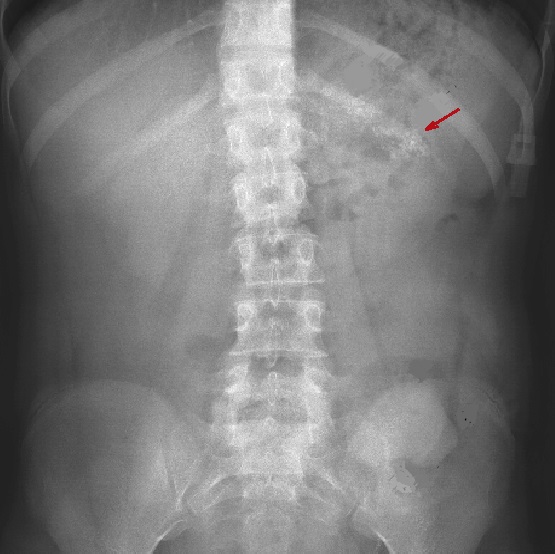

Le cliche de ASP

et les examens de opacification

digestive ; Sont des techniques le plus interet

dans le bilan de la pathologie pancreatique : Le cliche de

face ASP peu se donne des image de calcification dans les

pacreatites chroniques calcifiantes .

| |

Le cliche de face seul peut

declenche des calcification du pancreas dans les

pancreatite chronique ou des tumeurs pancreatiques

|

Une meme cas de pancreatite chonique . On

peut en voyant des nodule de calcifie du queue du

pancreas ( fleche rouge ) . |